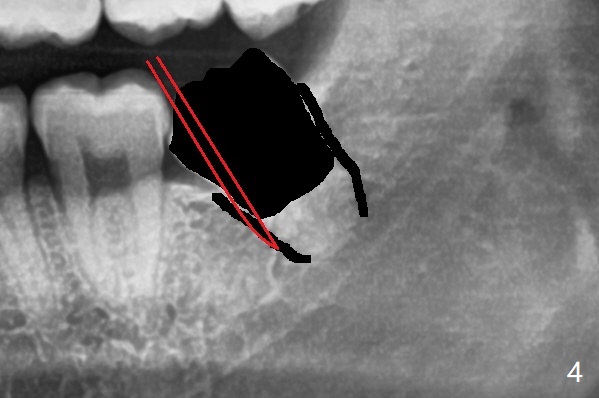

牙冠去除后(图三:黑色),容易插入根尖挺(图四:红色,因为事先根尖周围间隙已经形成)